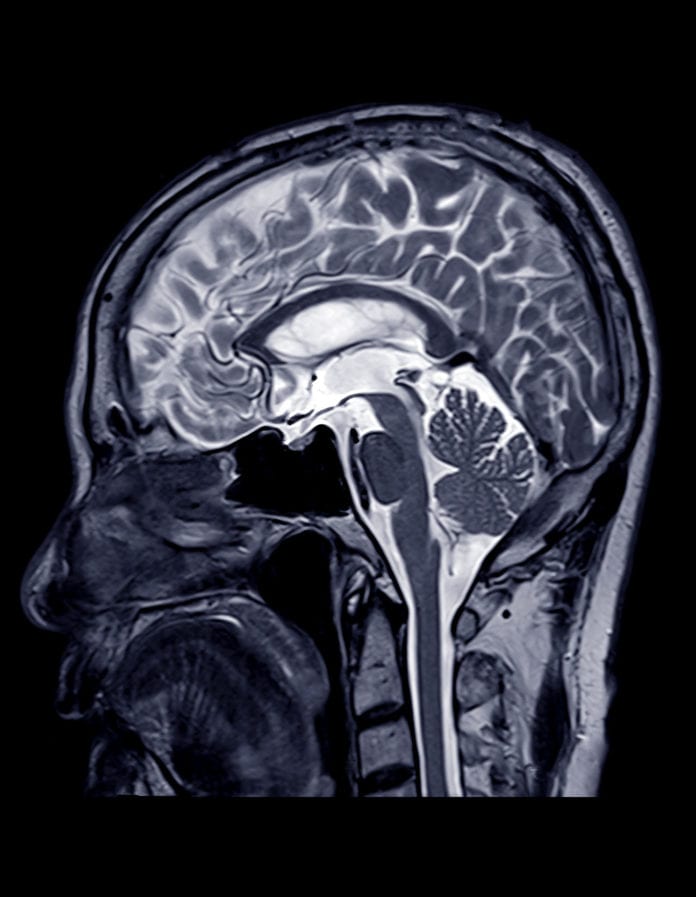

“Aneurysms are an enlargement of a blood vessel in the body,” says Beau Hawkins, a cardiologist with OU Health in Oklahoma City. “They most commonly affect arteries, which are vessels that distribute blood flow from the heart to the rest of the body.”

Hawkins says aneurysms can affect any blood vessel, but most often occur in the aorta and the...